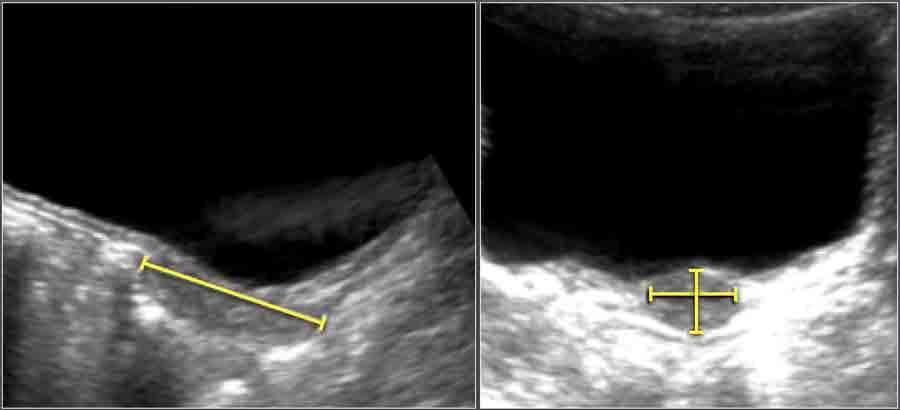

Khoang dưới nhện

Vật liệu và Phương pháp

Đánh giá siêu âm khoang dưới nhện được thực hiện trên 278 trẻ sơ sinh đủ tháng khỏe mạnh người Trung Quốc.

Các số đo được thực hiện trên mặt phẳng coronal tại mức lỗ Monro.

Các giá trị trung bình được tính từ phương trình hồi quy, và khoảng tin cậy 95% được tính toán từ dữ liệu đã công bố.

Các thông số siêu âm

- SCW: Chiều rộng xoang-vỏ não (Sinu-cortical width)

- CCW: Chiều rộng sọ-vỏ não (Cranio-cortical width)

- IHW: Chiều rộng liên bán cầu (Interhemispheric width)